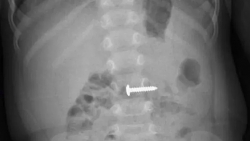

Bệnh viện Đa khoa tỉnh Quảng Trị cho biết, các bác sĩ vừa thực hiện nội soi, gắp dị vật là chiếc đinh vít cho bé trai 34 tháng tuổi.